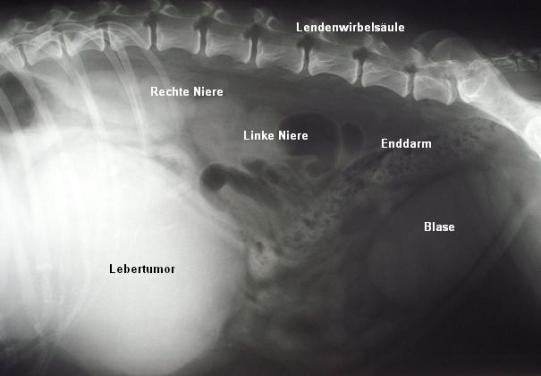

Es ist ein Knoten von ca. 20 cm Durchmesser im vorderen, unteren Teil des Bauchraumes sichtbar. Die Masse liegt teilweise unter dem Rippenbogen. Der Magen ist aufgrund der Masse gegen die Wirbelsäule verdrängt. Verdacht: Lebergeschwulst.